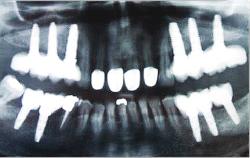

Implantología

Imagen en alta resolución. Este enlace se abrirá mediante lightbox, puede haber un cambio de contextoLas modernas técnicas de implantología se basan en la inserción en los huesos maxilares de implantes de titanio, los cuales en un porcentaje superior al 95% se osteointegran en dichos huesos, permitiendo la reposición de los dientes perdidos. Estas técnicas están avanzando constantemente, pudiéndose en la actualidad solucionar desde los problemas más sencillos, como puede ser la falta de estabilidad de prótesis en personas mayores, hasta las rehabilitaciones completas fijas más complejas en pacientes que presentan pérdida de hueso. Estos casos, en los que antes era imposible la inserción de implantes, hoy en día se pueden resolver realizando técnicas quirúrgicas para reconstruir el hueso, tal como injertos óseos ó aumento del mismo mediante distracción alveolar. En casos con defectos menores pueden aplicarse biomateriales sintéticos, mientras que en caso de grandes defectos se utilizará el propio hueso del paciente. El uso en los casos en que se indique de factores de crecimiento derivados de las plaquetas del paciente (PRP), podría mejorar la calidad del lecho a implantar.